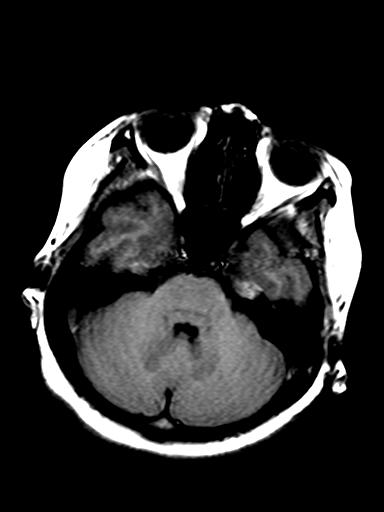

发热、头痛伴精神异常1周

脑炎,肾上腺性脑白质营养不良待除外

较对称性脑白质异常信号,深部白质t2明显低信号(铁质沉积过多?)

考虑脑白质病变,请结合临床病史及实验室检查进一步分析。